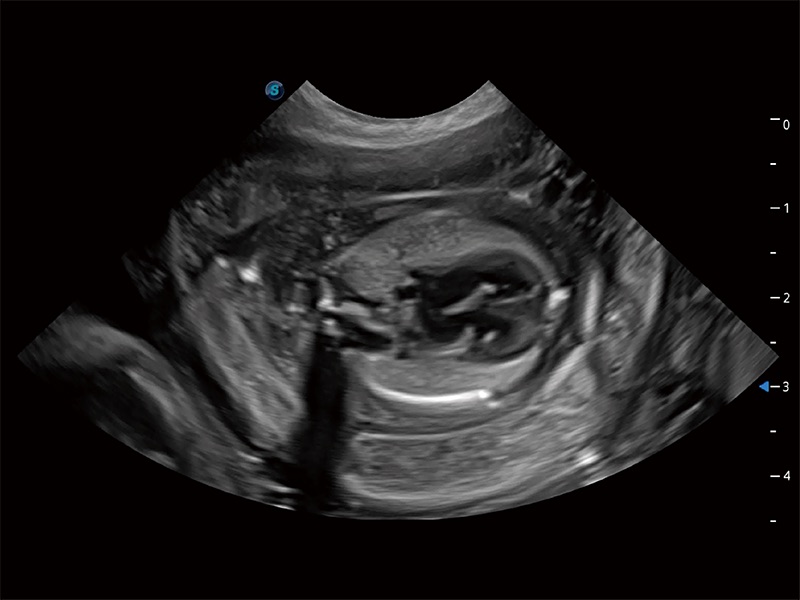

动物是人类最亲密的朋友和最值得信赖的伙伴。狗万官方网站也一直致力于探索动物专用的超声影像解决方案。全新推出的ProPet系列,是狗万官方网站在动物超声影像智能化、专业化、精准化的一次跨越式革新。动物不能用言语来表述自己的不适,通过超声影像,ProPet系列搭建了动物医生与不同物种沟通的“桥梁”,为动物医生注入了“治愈之力”。 ProPet 80 是狗万官方网站匠心打造的一款高端动物专用彩超,采用性能卓越的全新硬件架构,极大提升超声系统的运行效率和数据处理能力,帮助动物医生从容应对日益增多的挑战性病例和日益多样化的临床需求。

高性能和先进的临床应用工具可以为动物医生提供临床信心。ProPet 80 搭载了先进的腹部和浅表应用工具,帮助医生在日常临床实践中发挥前所未有的作用。